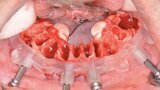

Fig. 10: Maxillary bone levelling guide.

Fig. 11: Maxillary implant surgical guide.